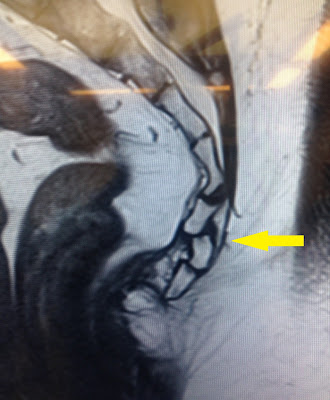

Tıbbi olarak kuyruk sokumu kemiğinin çekilmesi için tek şart vardır. O da kuyruk sokumu kemiği çıkığıdır. Eğer hasta travma sonrası 3 gün içinde gelirse yani akut çıkık varlığında ameliyathanede anestezi altında çekme işlemi( Tıbbi adı redüksiyon) uygulanır. Eğer 3 günden eski çıkık ise çekme işleminin faydası yoktur, bu nedenle yapılmaz